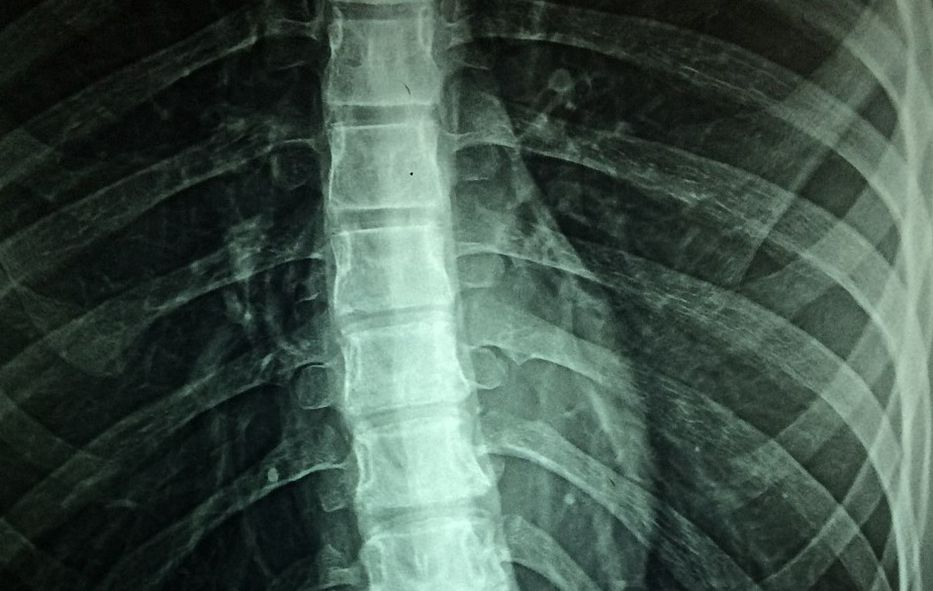

La médula espinal es una parte vital del sistema nervioso central, y su salud es fundamental para el funcionamiento de diversas actividades vitales en humanos y primates, informó hoy la agencia de noticias Xinhua.

A pesar de su importancia, el conocimiento limitado sobre cómo envejece y cómo afecta el envejecimiento a esta región del cuerpo no ha permitido un mayor desarrollo de tratamientos relacionados.

El descubrimiento de las microglías y su conexión con el envejecimiento de la médula espinal proporciona una visión más profunda de la biología subyacente en el proceso de degeneración y las enfermedades crónicas que afectan a la población anciana.